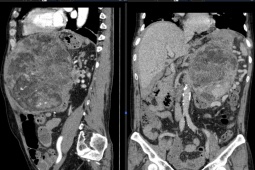

Phơi nhiễm tia UV cao là nguyên nhân gây ung thư đáng lo ngại, ngày càng gia tăng - Ảnh: MEDICAL XPRESS